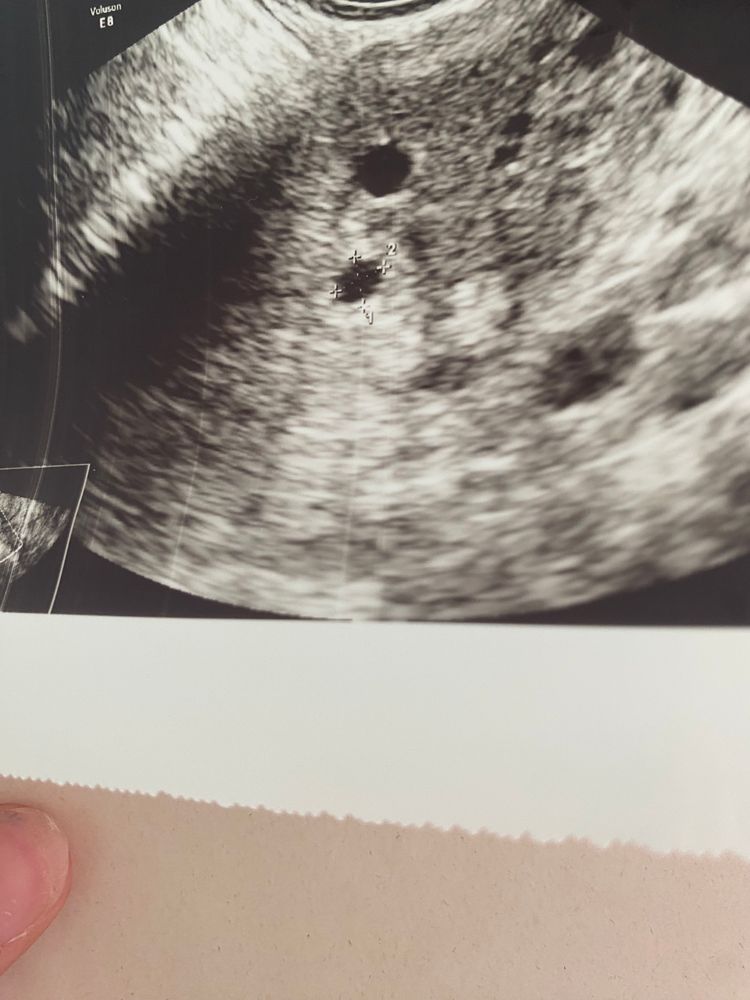

Анализы и процедуры. Помощь в расшифровке результатовсходила я на узи. В клинике где делала эко увидели в левой трубе что-то похожее на плодное яйцо… Дали направление на госпитализацию… приехала я в больницу, сделали узи и ничего не увидели… я в истерике просто.. не знаю что мне уже делать. Вчера хгч был 720… сегодня еще раз утром сдала… вечером придет результат… прикладываю фото узи.. кружочек что поменьше сказали плодное яйцо